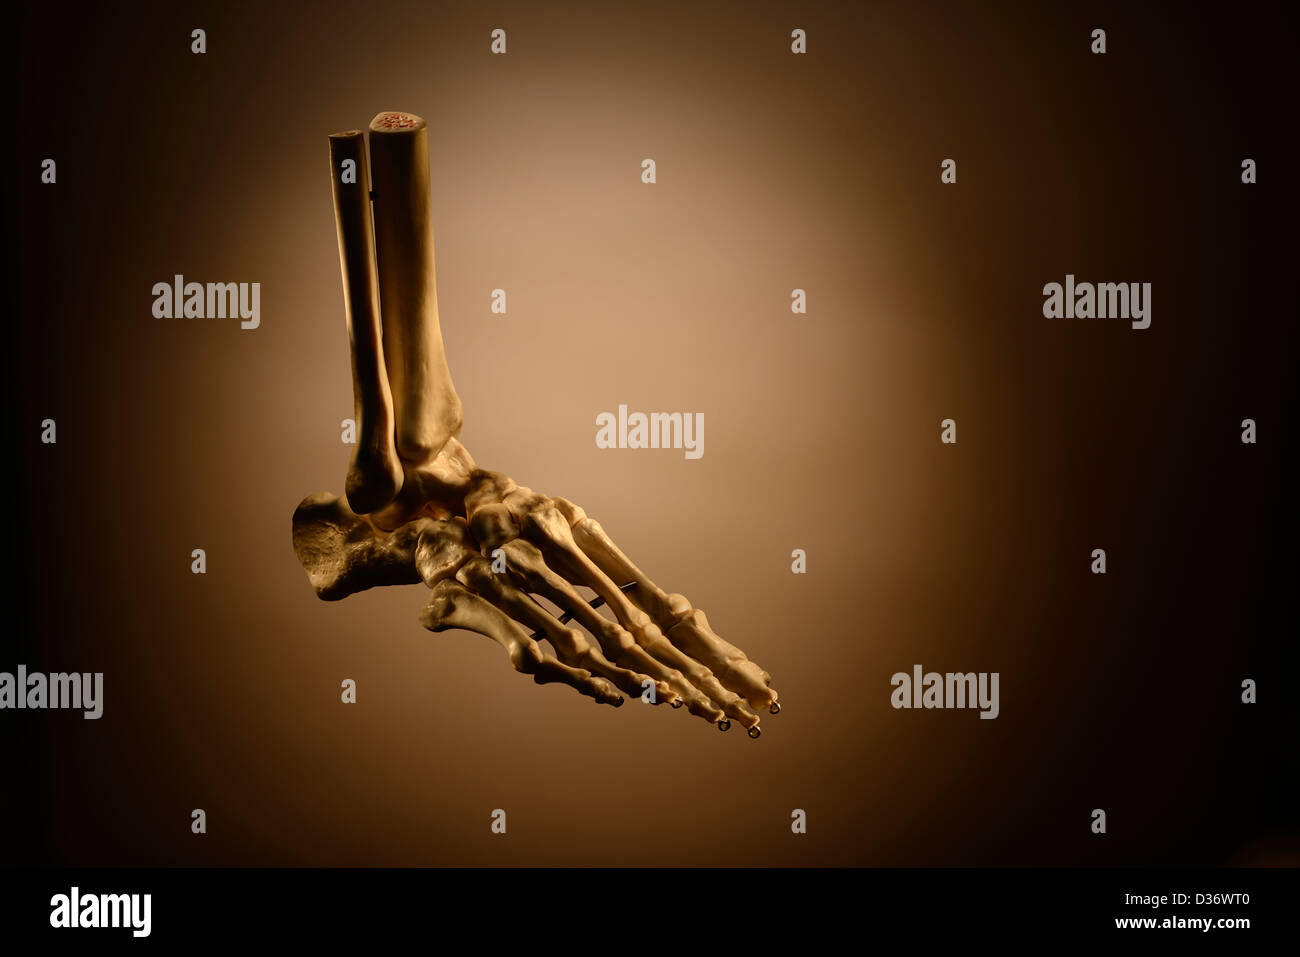

RMK228DY–Partie terminale du membre inférieur, reposant sur le sol au cours de posture droite ; le squelette du pied a 26 os.

RMK227XM–Partie terminale du membre inférieur, reposant sur le sol au cours de posture droite ; le squelette du pied a 26 os.